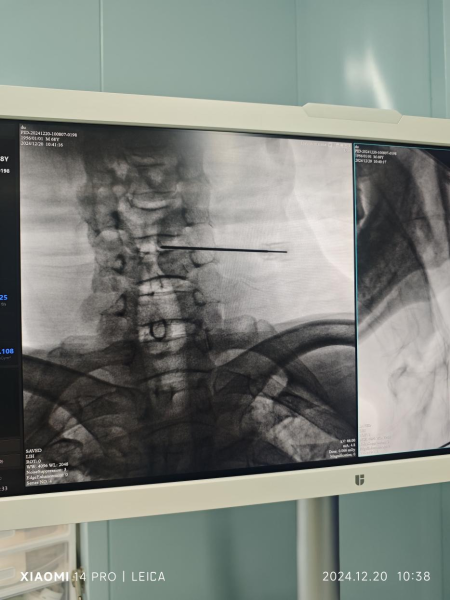

2024年12月20日,骨科李开南主任主刀,在无需麻醉情况下,利用直径0.9 毫米的弹力导针精准穿刺定位颈5/6椎间盘,置入激光光纤,使用2W 970nn激光强度治疗4分30秒后,患者术中当即诉说感到头部昏沉症状得到明显改善及颈肩痛症状也有缓解。术后两天患者基本恢复正常生活,术后一周顺利出院。

(图1,图2患者术中定位)

(图3,图4为术中穿刺定位透视)